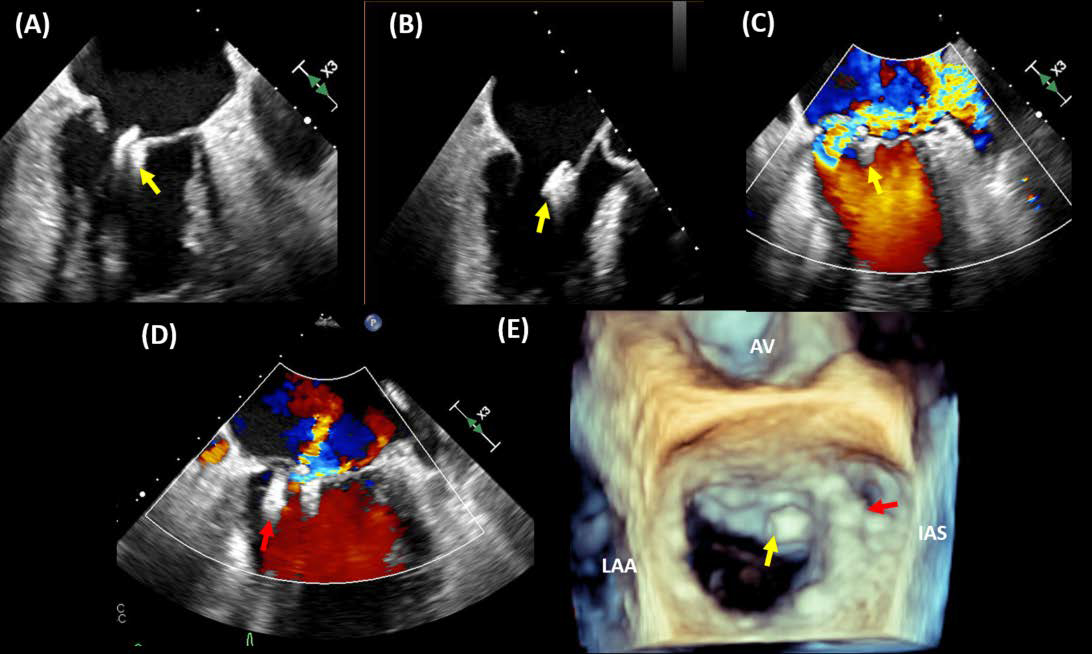

Single leaflet device attachment (SLDA) describes and entity in which there is disengagement of insertion of one of the leaflets from the MitraClip device and can occur in 2–5% of cases. This entity can occur during the procedure or follow-up [17, 18, 42, 45]. One of the most important tasks of the structural heart imager entails the acquisition of high-resolution grasping views that display leaflet insertion into clip arms ensuring a good grasp with both leaflets tucked in the closed device. Some strategies to stabilize SLDA include the deployment of additional clips if feasible [40, 47, 48]. Fig. 5 shows TEE imaging demonstrating the attachment of the clip to a single leaflet.

Fig. 5.Single leaflet detachment. A case of single leaflet device attachment (SLDA). A patient with previous transcatheter edge-to-edge repair of the mitral valve presents with heart failure symptoms and TEE imaging showing SLDA of the MitraClip device (yellow arrow). The device was attached to the anterior leaflet (A&B) with severe mitral regurgitation (C). A second MitraClip device (red arrow) was deployed medial to the first device, resulting in mild residual MR (D). 3 TEE imaging shows the newly implanted device at A3-P3 in relation to the first device that has detached from the posterior leaflet (E). AV, aortic valve; LAA, left atrial appendage; IAS, interatrial septum.